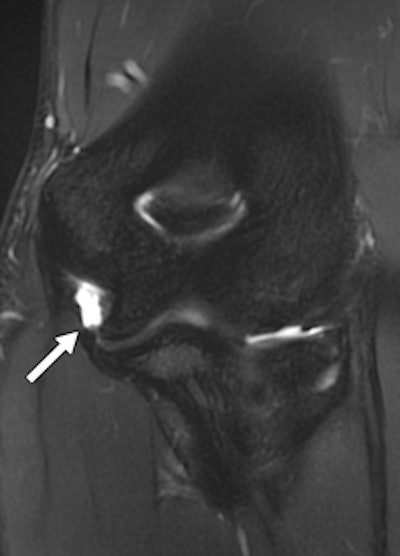

A 22-year-old female boxer who sustained direct blow to elbow during bout. Left: Radiograph of elbow shows avulsion fracture (arrow) of lateral epicondyle. Right: Coronal proton density-weighted fat-saturated MRI shows radial collateral ligament avulsion (short solid arrow). Note edema of lateral epicondyle at site of avulsion (open arrow), complete tear of proximal UCL, and superficial common flexor tendon (long solid arrow).